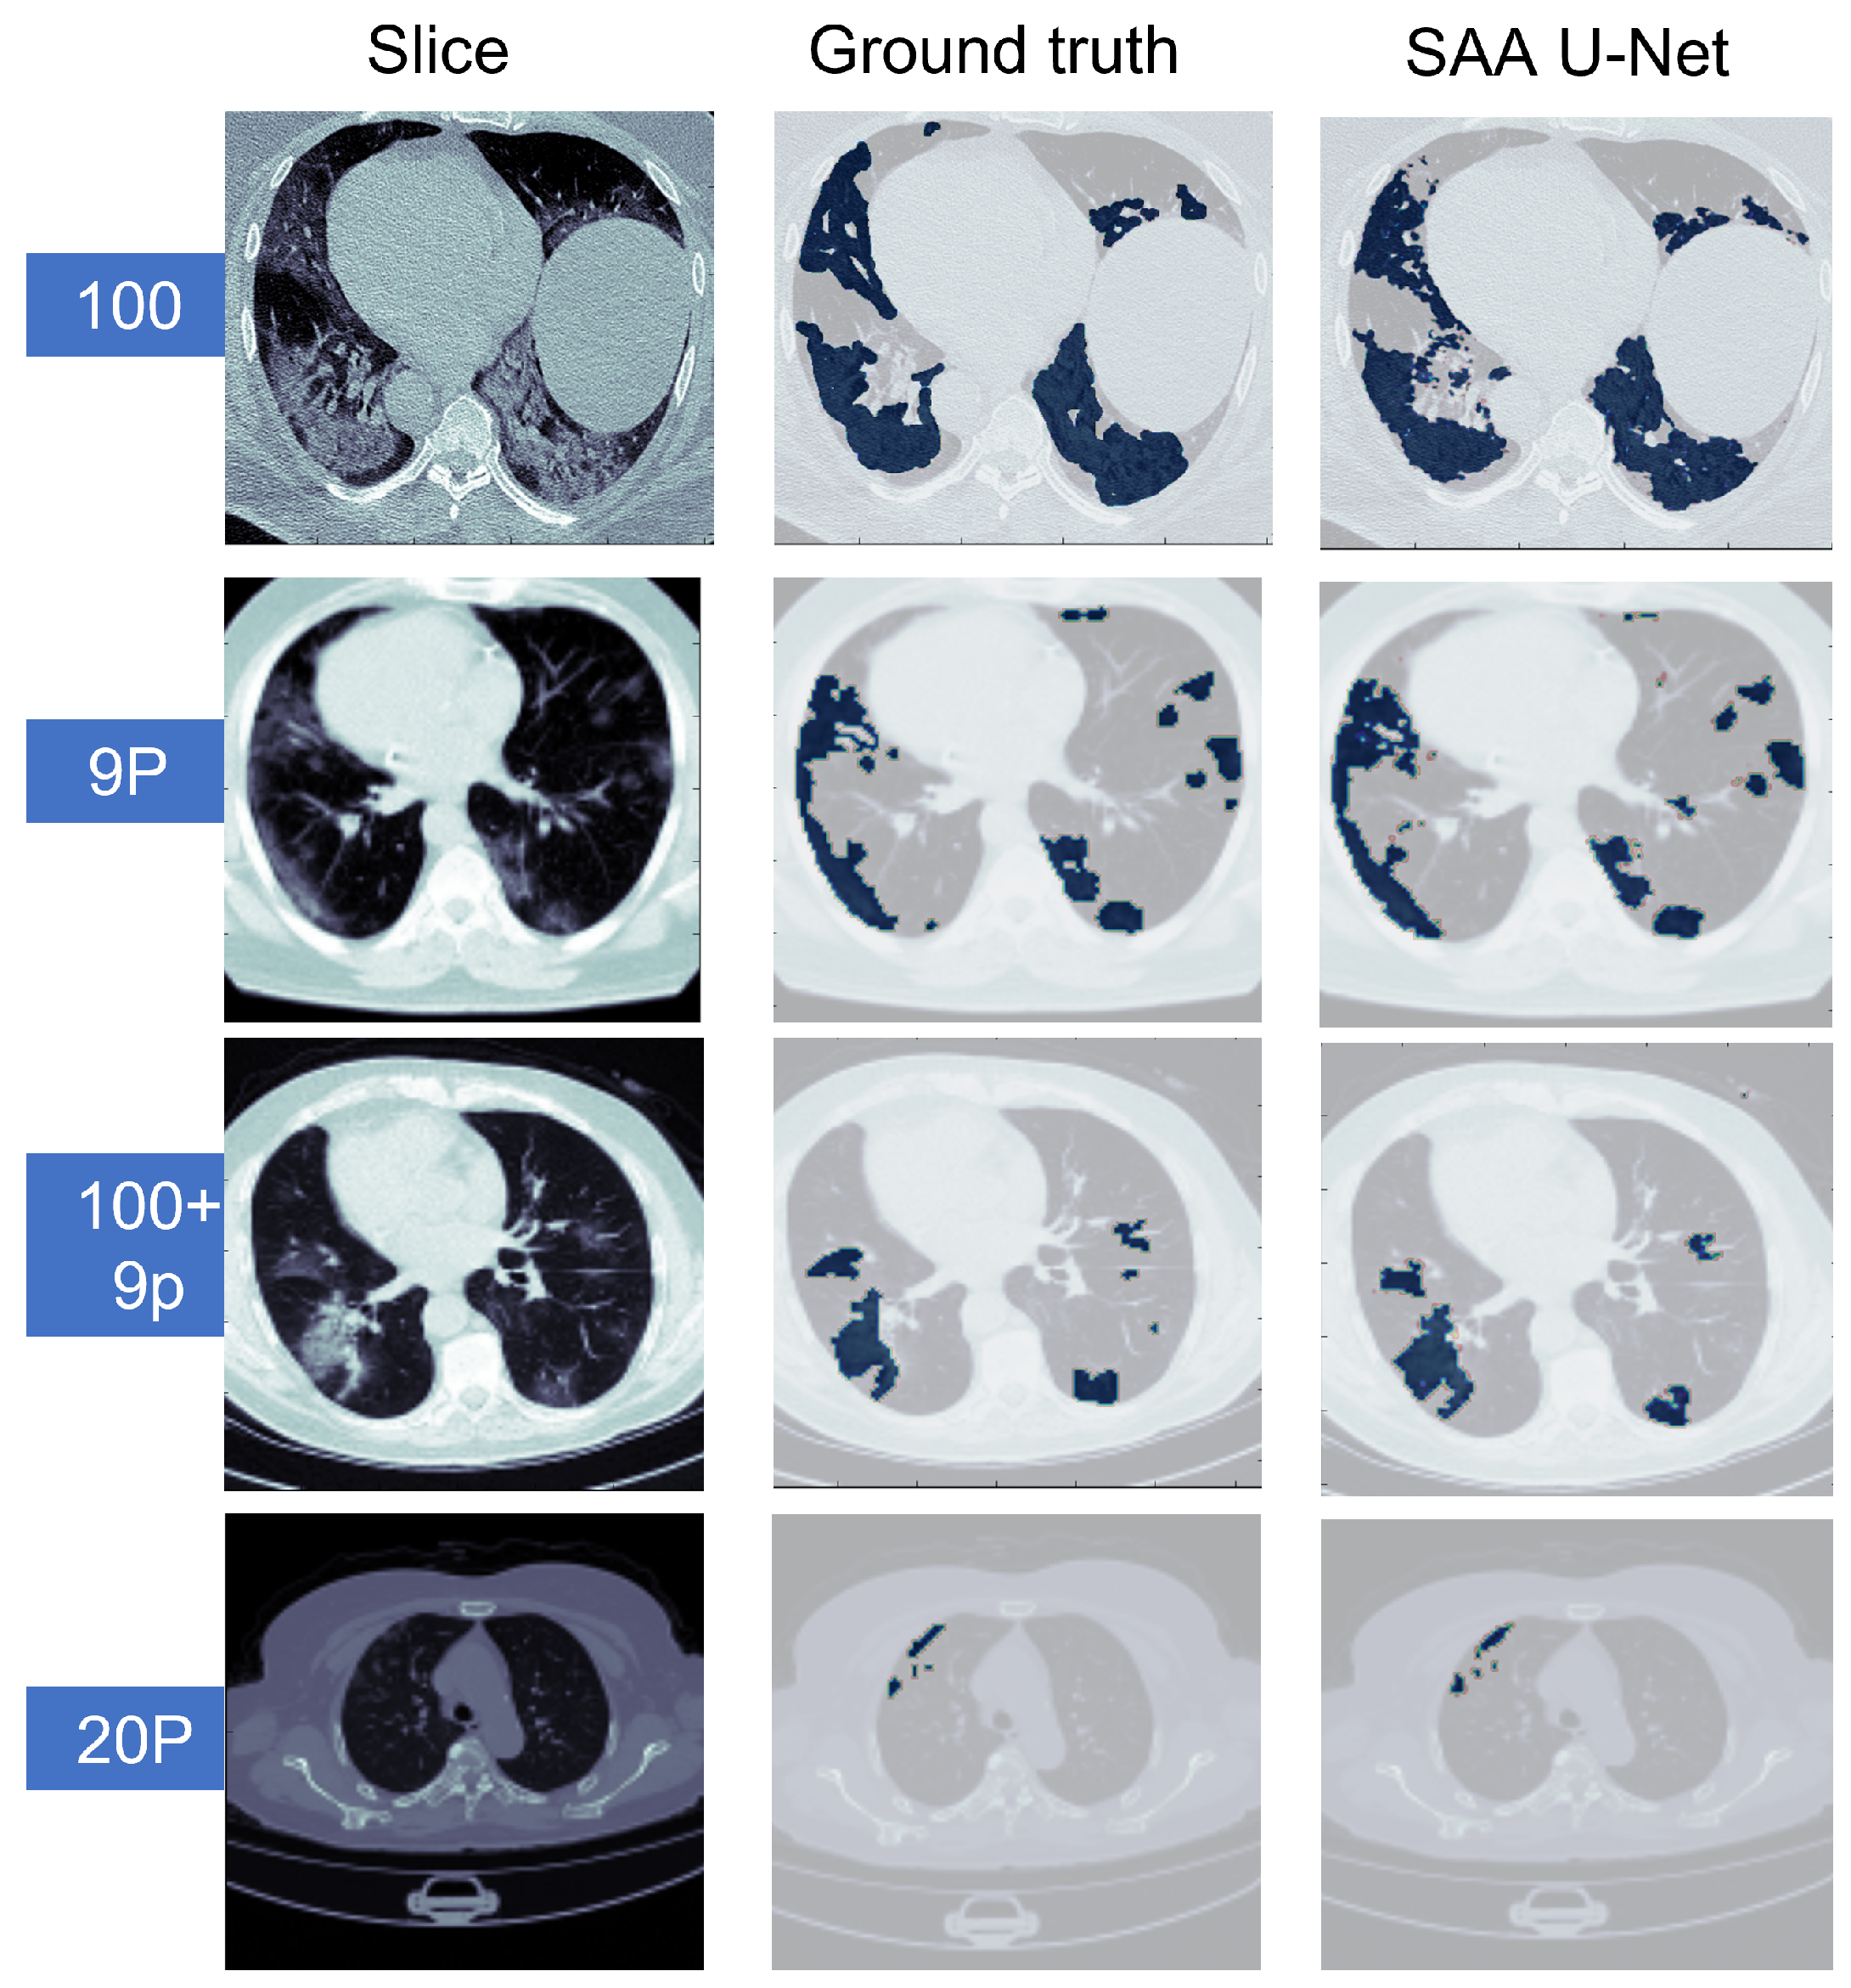

Figure 13.

The predicted CT slices of the best fold for each dataset in multi-class segmentation. In the first three datasets, white is for GGO, grey is for consolidation, green is for lungs, and brown is for the background. For the last dataset, white is for infection, brown for the left lung, grey for the right lung, and lighter greyfor the background.

Some sample predicted slices of the three datasets with COVID-19 infection pixels are illustrated in Figure 13. It shows that SAA-UNet had a good prediction of the ground truth. The confusion matrix of each dataset for the SAA-UNet model appears in Figure 14. For the MedSeg dataset, both the GGO and Con classes were confused with the lung class (25% and 11%, respectively). The same trend to a lesser extent was observed for the Radiopaedia 9P dataset as well.